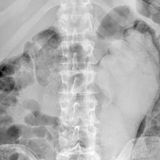

Diese Dinge gehören dort eigentlich nicht hin: Immer wieder passieren Unfälle, wenn Menschen sich zur sexuellen Stimulation über den After Gegenstände in den Darm einführen. Ob Orangen, Spraydosen oder Kaffeebüchsen - der Fantasie sind dabei offenbar keine Grenzen gesetzt.

Die Webseite radiopaedia.org zeigt, welche Dinge Ärzte auf Röntgenbildern schon entdeckt haben. Die Aufnahmen wirken skurril und erschreckend zugleich und machen deutlich, wie weit die eingeführten Dinge bereits in den mescnhlichen Darm vordringen können.

Aber Glück im Unglück für die Patienten: Die Gegenstände können meist ohne Operation entfernt werden. Sehen Sie hier einige der spektakulärsten Röntgenaufnahmen. Da runzeln selbst Chirurgen die Stirn.